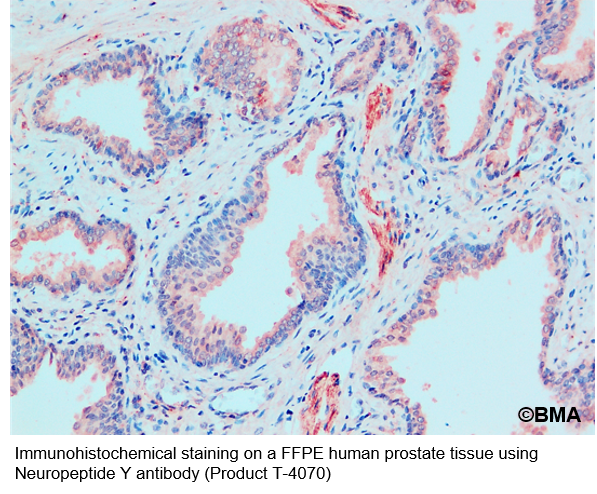

Wählen Sie die passende Anwendung: Wählen Sie die Anwendung, die am besten zu Ihrer Forschung passt. Dies hängt von der Art der Daten ab, die Sie zur Beantwortung Ihrer Forschungsfrage benötigen. Beispielsweise ist Western Blot eine bekannte Methode zur Untersuchung der Proteinkonzentration; Immunhistochemie und Immunzytochemie werden zur Untersuchung der Lokalisation eingesetzt, da sie mit fixierten Zellen und Geweben arbeiten; ELISA, FACS und Durchflusszytometrie hingegen sind geeignete Techniken zur Untersuchung von Proteininteraktionen und -expression.

222.png